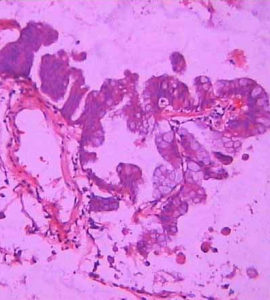

肺泡細胞癌 小細胞肺癌生長較快,倍增時間短,約為25-46天,平均約為30天,分化差,惡性程度高,早期易出現轉移,確診時約有70%-90%的 病人已有縱隔淋巴結和(或)胸外器官廣泛轉移,對化療、 放療敏感。 小細胞肺癌的手術療法通常認為,所有經組織學、細胞學或臨床診斷肺癌的患者,只要 病期 在Ⅱ期以前,且無絕對禁忌症,都可列為手術適應對象。但由於小細胞癌惡性程度高、轉移早,一般認為不宜手術治療。也有人提出,對於早期發現的年青人原發性肺癌,應當採用根治性外科治療。小細胞肺癌的放療由於單純用化療治療小細胞肺癌的胸腔局部 復發率 高,所以主張在化療過程中,輔以胸腔原發灶的 放療 ,以提高胸內腫瘤的局部控制率。